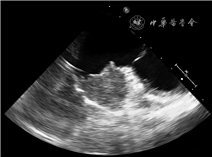

患者女,26岁,主因“间断胸痛、胸闷、呼吸困难40余天”于2019年10月22日入院。患者40余天前出现间断胸痛、胸闷、呼吸困难症状,伴乏力、口唇紫绀、恶心呕吐,呕吐物为胃内容物,后出现右上腹疼痛伴右侧肩部疼痛。否认高血压及其他心脏病史,无家族遗传病史。入院体格检查:血压95/52 mmHg(1 mmHg=0.133 kPa),心率108次/min,律齐,肝颈静脉回流征阴性,双肺呼吸音低,各瓣膜区未闻及杂音。PET-CT(图1):右心房区见放射性浓聚灶,最大标准摄取值(SUVmax)约7.1,大小约4.1 cm×2.2 cm,心包见液性密度影,其余各系统未见浓聚灶。超声心动图:右心房近上腔静脉侧可探及范围约3.9 cm×1.9 cm低回声光团附着,形态规则,边界欠清,心包腔内可探及中量液性暗区。术前经食道超声心动图再次确认为右心房占位性病变(图2)。